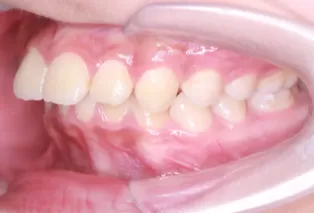

Intraoral photos